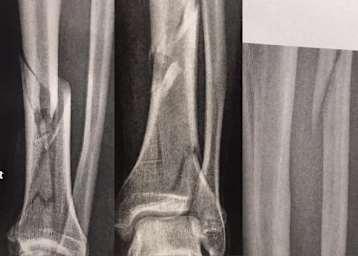

In der Startaufstellung zu den beiden Rennen in den Niederlanden im Rahmen des vierten IDM-Superbike-Wochenendes werden Sarah Heide und Patryk Kosiniak fehlen. Knochen entzwei und Knie hinüber.